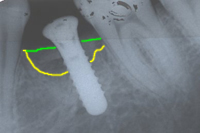

Abb. 6 zeigt den Verlust eines unteren Milchzahnes bei einem 26 Jahre jungen Patienten. Gesunde Nachbarzähne veranlassen uns, ein Implantat vorzuschlagen und auf eine Brücke zu verzichten, welche das Beschleifen der Nachbarzähne nötig gemacht hätte. Stark erschwerend ist allerdings, dass im Röntgenbild von Abb. 6 ein grosser Knochenkrater sichtbar ist.

Abb. 7 zeigt, wie das Knochentransplantat aus dem Kinn fixiert wird, um den Knochenkrater zu füllen. Nach viermonatiger Einheilung (Abb. 8) setzen wir das Implantat.

| Ursprünglicher Verlauf des Kieferkammes | |

| Neuer Verlauf des Kieferkammes | |

| Gebiet zwischen gelber und grüner Linie: Knochenaufbau | |

Im Röntgenbild von Abb. 9 sieht man, dass dreieinhalb Jahre später absolut perfekte Knochenverhältnisse ums Implantat herrschen. Abb. 10 zeigt die klinische Situation dreieinhalb Jahre nach dem Zementieren der Implantatkrone.